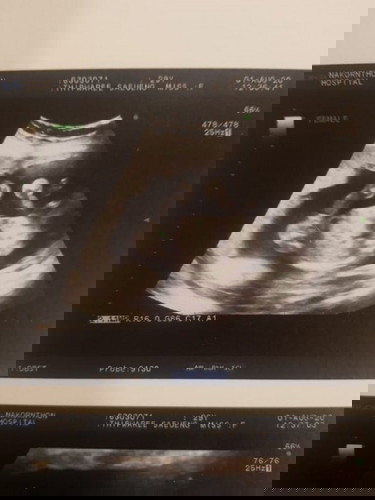

คุณหมอบอกว่าลูกสาว 100% ค่า แถมยังชี้ลูกศรให้ดูด้วย แต่แม่ดูไม่ออก555 ช่วยบรรยายหน่อยไหนมั้ยคะ☺️

* ถ้าชายจะมีจู๋โผล่ระหว่างหว่างขาค่าแม่

ไอ้ที่ยื่นออกมาสองข้างนั่นขาเค้าใช่มั้ยคะ แม่งงว่าทำไมลูกศรไปชี้ตรงนั้น555